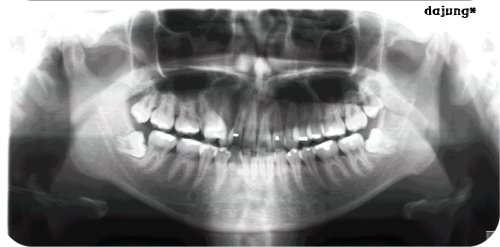

다죵_*

사랑니를 뽑아야 할까? 말하야 할까?

우리끼리 질문방에 올렸다가 삭제하고 다시 올려요.. 답변 기다립니다 ㅠ-ㅠ 제 엑스레이 사진인데요.. 치아 몇개 뽑아야 해요? 옆에 누워 있는 사랑니를 안뽑아도 괜찮아요? 오늘 의사선생님이 안뽑아도 괜찮다고 나...

전문의 답변 1